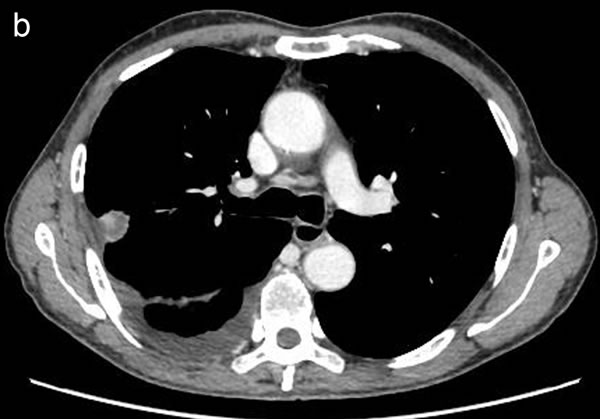

Figure 2: Representative CT images showing homogeneous enhancement (a) and heterogeneous enhancement (b).

CT image analysis and post-processing

Two radiologists (with 6, and 3 years’ experience in thoracic CT imaging, respectively), who were blinded to clinical and histiopathological data, reviewed all CT images separately. They were asked to identify pulmonary lesions and to evaluate the enhancement heterogeneity according to the following criteria: homogeneous enhancement was defined as more than 90% of the tumor area was occupied by the same CT attenuation as ascertained by visual assessment; otherwise heterogeneous enhancement was considered (Figure 2). In case of disagreement, the third reviewer with 27 years of clinical experience in thoracic imaging, made the final decision. Then, semiautomatic tumor segmentation was done in consensus by three radiologists using a designated multi-platform, free and open source software package for visualization and medical image computing (3D slicer, version 4.4.0; available at: http://slicer.org/) (Figure 3). Totally, 54 features were extracted and they were divided into four categories (Supplementary Table 1, Image features metrics are available at: https://www.slicer.org/wiki/Documentation/Nightly/Modules/HeterogeneityCAD), including (1) First-Order Statistics, (2) Morphology and Shape, (3) Texture: GLCM, and (4) Texture: GLRL.